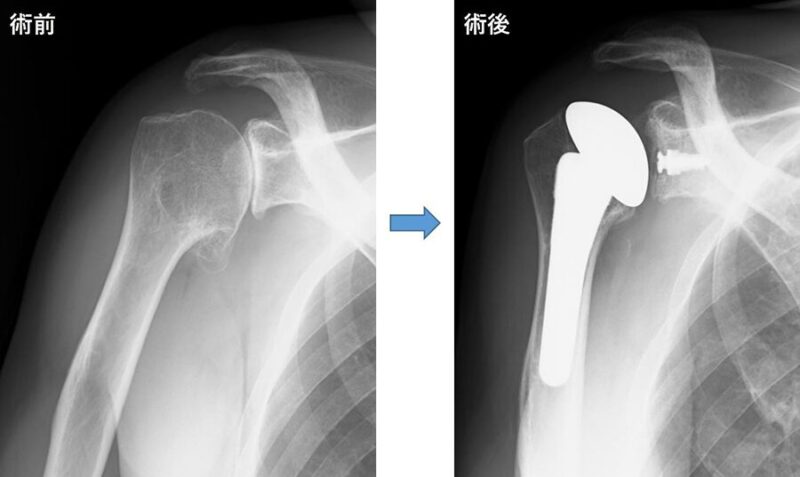

肩関節の重度の破壊や機能障害に対しては、人工肩関節全置換術(TSA)や、上腕骨頭のみを人工骨頭に置き換える人工骨頭置換術(HA)が有効な治療法です。これらの手術は、痛みの緩和や関節機能の改善を目的とします。

人工肩関節全置換術(TSA)

- 概要: 肩甲骨と上腕骨の両方の関節表面を人工材料に置き換える手術です。

- 適応: 主に、肩甲骨の受け皿と上腕骨の骨頭の両方が傷んでいる変形性肩関節症や、関節リウマチなどが対象となります。

- 目的: 痛みの軽減と関節動作の改善が期待されます。

人工骨頭置換術(HA)

- 概要: 上腕骨の骨頭のみを人工骨頭に置き換える手術です。

- 適応: 上腕骨の骨頭部分のみが傷んでいる変形性肩関節症や、上腕骨近位部骨折などが主な適応となります。

- 目的: 上腕骨頭の破壊による機能障害を改善します。